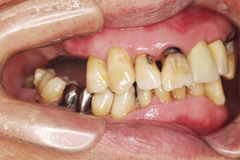

吉本歯科医院では、口内写真とパノラマレントゲンを撮影し、まずは顎の骨の状態まで詳しく確認しました。

写真(1)